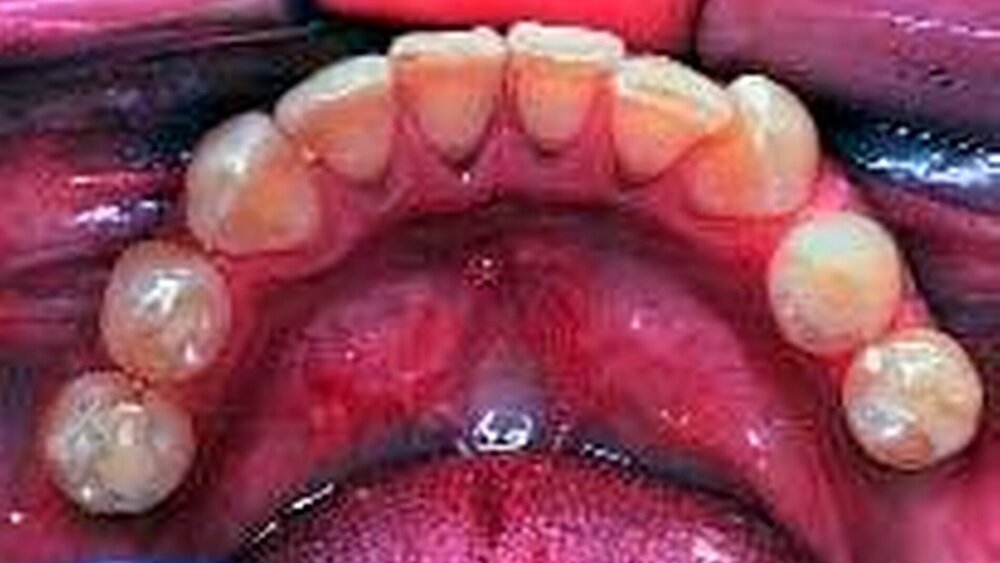

Dr. Peter Weigl, Frankfurt/ Main, berichtete über die Zukunft zahnärztlicher Prothetik in Bezug auf Hightech-Innovationen. Die Abhängigkeit der zukünftigen zahnärztlichen Prothetik von demographischen Entwicklungen, Kostendruck, Erwartungshaltung des Patienten, Werkstoffsystemen, Minimal-Invasität und Implantologie waren einige Hauptfaktoren seines Vortrages. Vorteile sowie neue Risiken für Patient und Behandler wurden aufgezeigt und an Hand gegenwärtiger Hightech-Innovationen kritisch hinterfragt. Dr. Alessandro Devigus, Buelach, Schweiz, diskutierte in seinem Vortrag „Digitale Bilder in der Praxis“ die Bedeutung der Digitalisierung der Zahnarztpraxis. Über die Grundlagen der Dokumentation, Kommunikation und Präsentation hinaus wurden Begriffe aus der professionellen dentalen Fotografie, sowie deren Bildbearbeitung anschaulich erläutert. Dr. Sven Markus Beschnidt, Filderstadt, und Dr. Alexander Krausse, Wachenheim, präsentierten in ihrem Hauptvortrag „(R)Evolution in Imaging“ den aktuellen Stand in der digitalen Videobearbeitung.